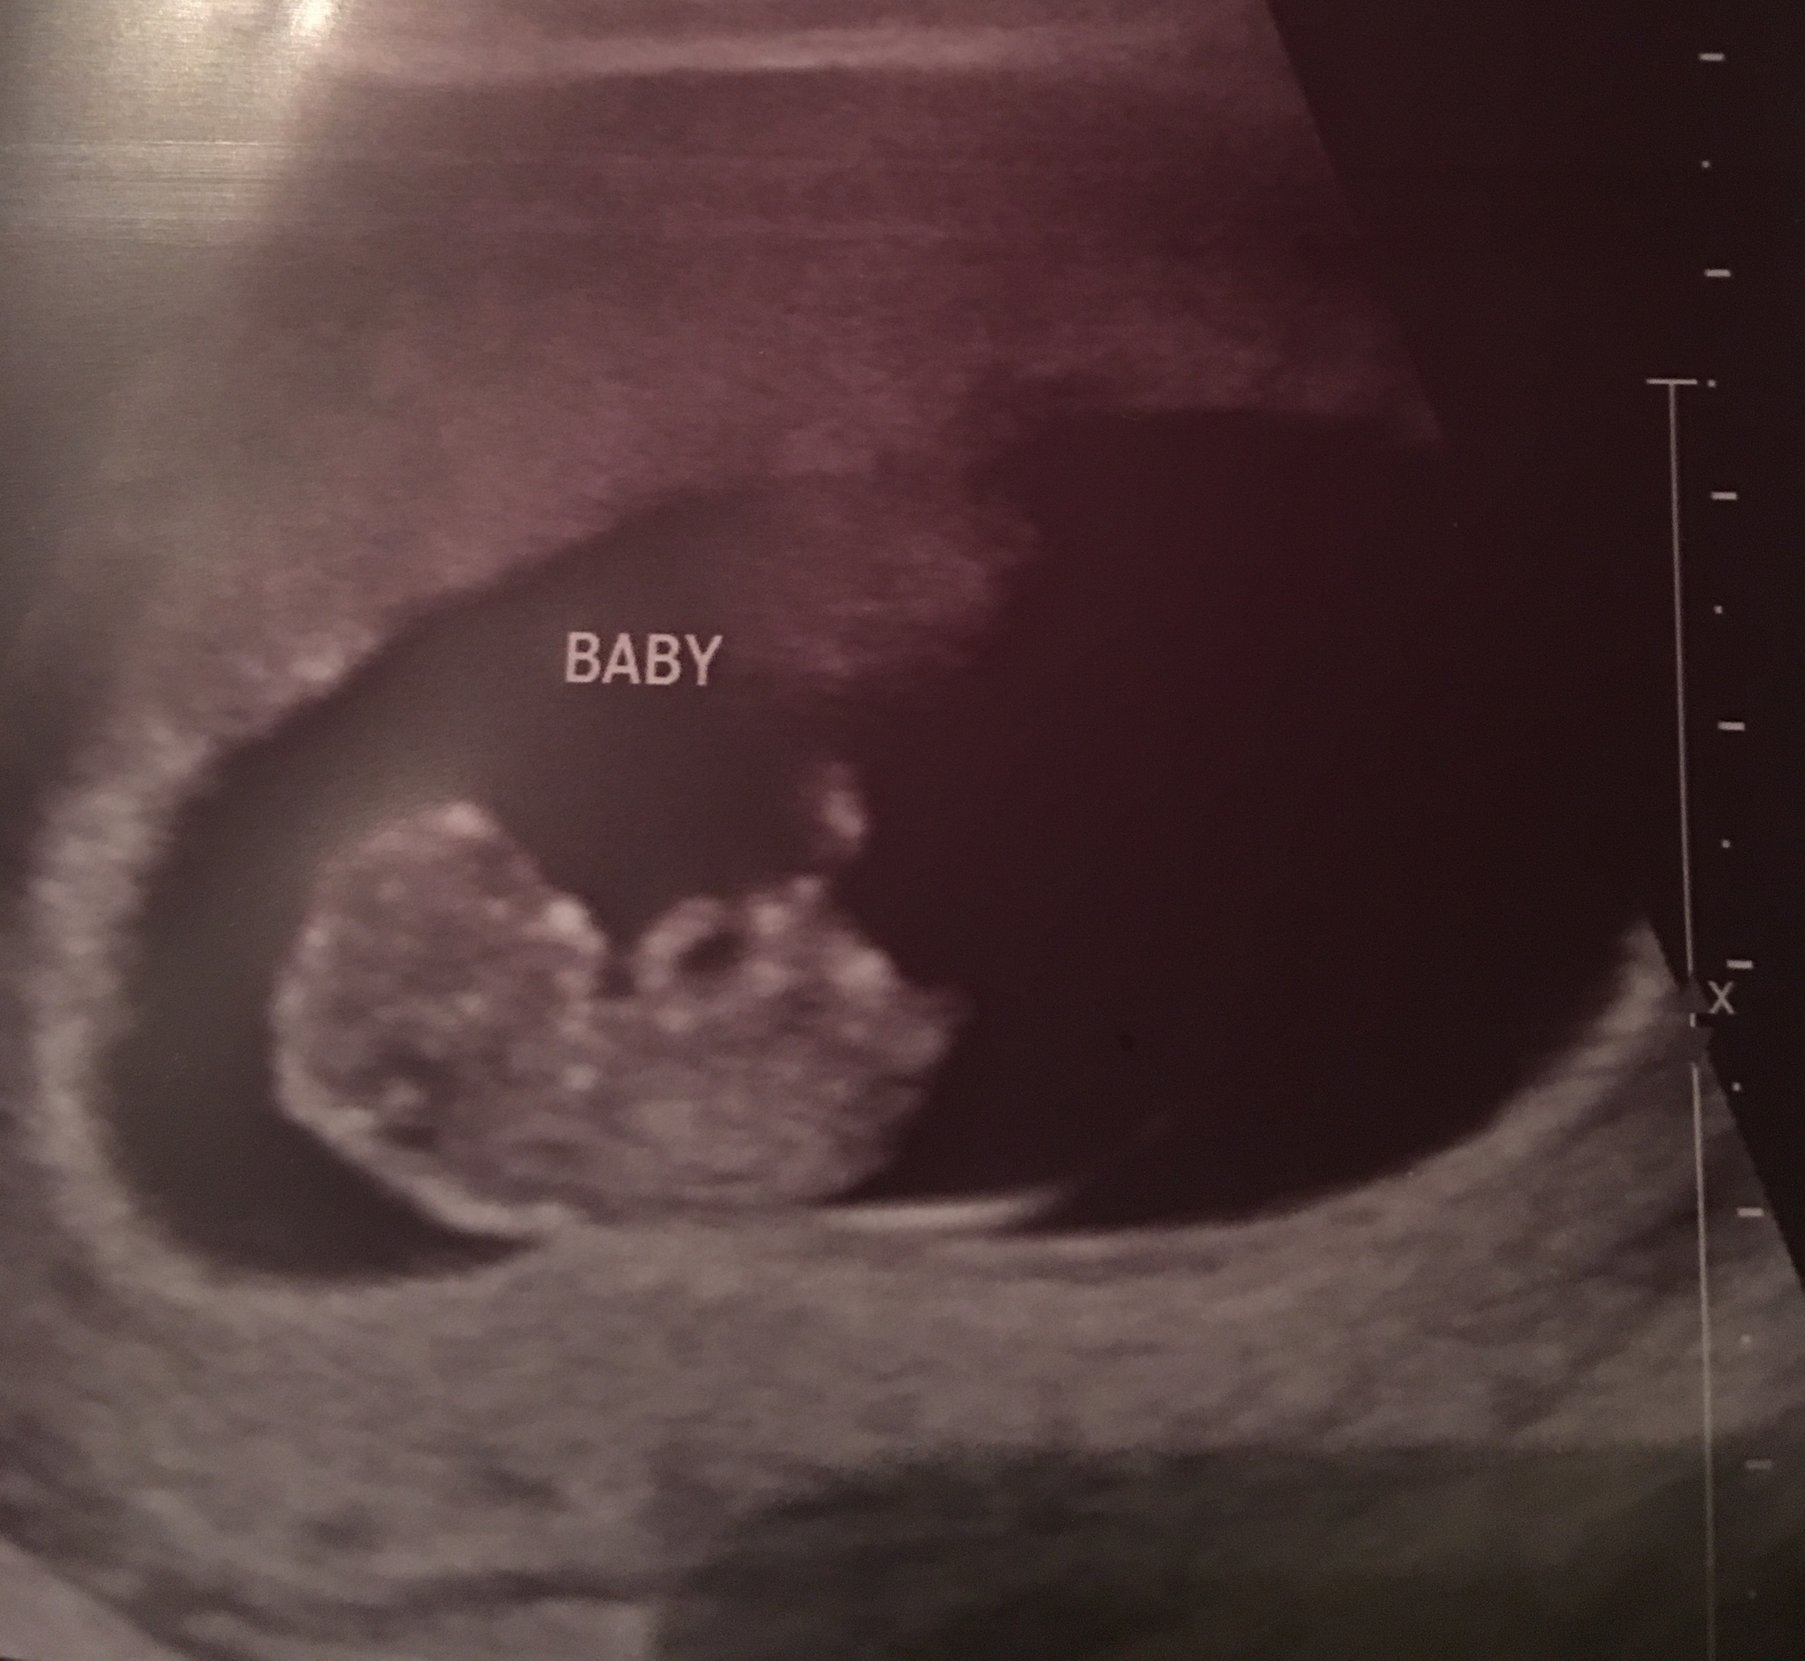

Our little baby!! 12 weeks 4 days and actually looking like a baby now it was so fun getting to watch it move around! This is my first pregnancy and due date is September 3rd!